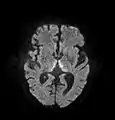

The most common application of conventional DWI (without DTI) is in acute brain ischemia. DWI directly visualizes the ischemic necrosis in cerebral infarction in the form of a cytotoxic edema,[38] appearing as a high DWI signal within minutes of arterial occlusion.[39] With perfusion MRI detecting both the infarcted core and the salvageable penumbra, the latter can be quantified by DWI and perfusion MRI.[40]

DWI showing necrosis (shown as brighter) in a cerebral infarction